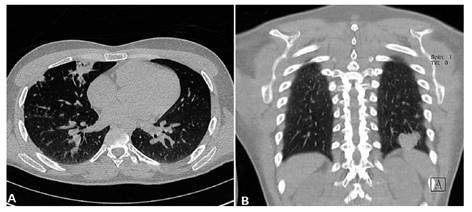

La analítica de ingreso mostró una leucocitosis con neutrofilia y linfopenia relativa y absoluta, resto de los exámenes dentro de parámetros normales (Tabla 1). En la resonancia magnética (RM) cerebral que trajo consigo mostró una lesión en núcleos basales izquierdos sugerente de un infarto cerebral debido a una probable vasculitis infecciosa (Figura 1). Se realizó una punción lumbar obteniéndose líquido cefalorraquídeo (LCR) con características inflamatoria crónica, consumo de glucosa, tinta china positiva, y un cultivo que posteriormente resultó positivo para Cryptococcus spp (Tabla 1). La tomografía de tórax mostró lesiones sugerentes de criptococosis pulmonar (Figura 2). Se diagnosticó criptococosis meníngea confirmada y pulmonar probable, iniciándose tratamiento con anfotericina B desoxicolato (AmBd) y fluconazol vía endovenoso.

Figura 2 Tomografía de tórax sin contraste. Se observan múltiples micronódulos con engrosamiento intersticial en ambos pulmones, y focos de consolidación en lóbulo medio derecho (A) y lóbulo inferior izquierdo (B).

Así mismo puede existir criptococosis en otros órganos simultáneamente, siendo el pulmón uno de los más frecuentemente afectados 1,14,18,19. Las manifestaciones pueden ir desde lo asintomático, hasta molestias inespecíficas como tos, dolor toráxico, fiebre o disnea, que usualmente se observan más en inmunocompetentes 14,19. Y hallazgos tomográficos como nódulos simples o múltiples, cavitaciones, lesiones tipo masa, o bronconeumonía, siendo estos 3 últimos hallazgos más típicos en pacientes VIH positivos, en contraposición a los nódulos simples que se ven más en inmunocompetentes 14,17,18,20. Nuestro paciente durante la hospitalización cursó con fiebre, dolor torácico y crepitantes basales que se correspondían con los hallazgos tomográficos. Los estudios de bacilo de Koch en esputo fueron negativos al igual que el cultivo de hongos en secreción bronquial, dado la baja sensibilidad de este último se concluyó como criptococosis pulmonar probable.